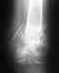

Re: Перелом плечевой кости

послал Alexander Chelnokov 10 Ноябрь 2016, 02:13

Что Вы сможете или нет - время покажет, когда начнете тренировки. Не стоит забывать о полученном опыте перелома вроде бы в привычной ситуации.

Сделано все неплохо.

Бессимптомные имплантаты нет необходимости удалять.